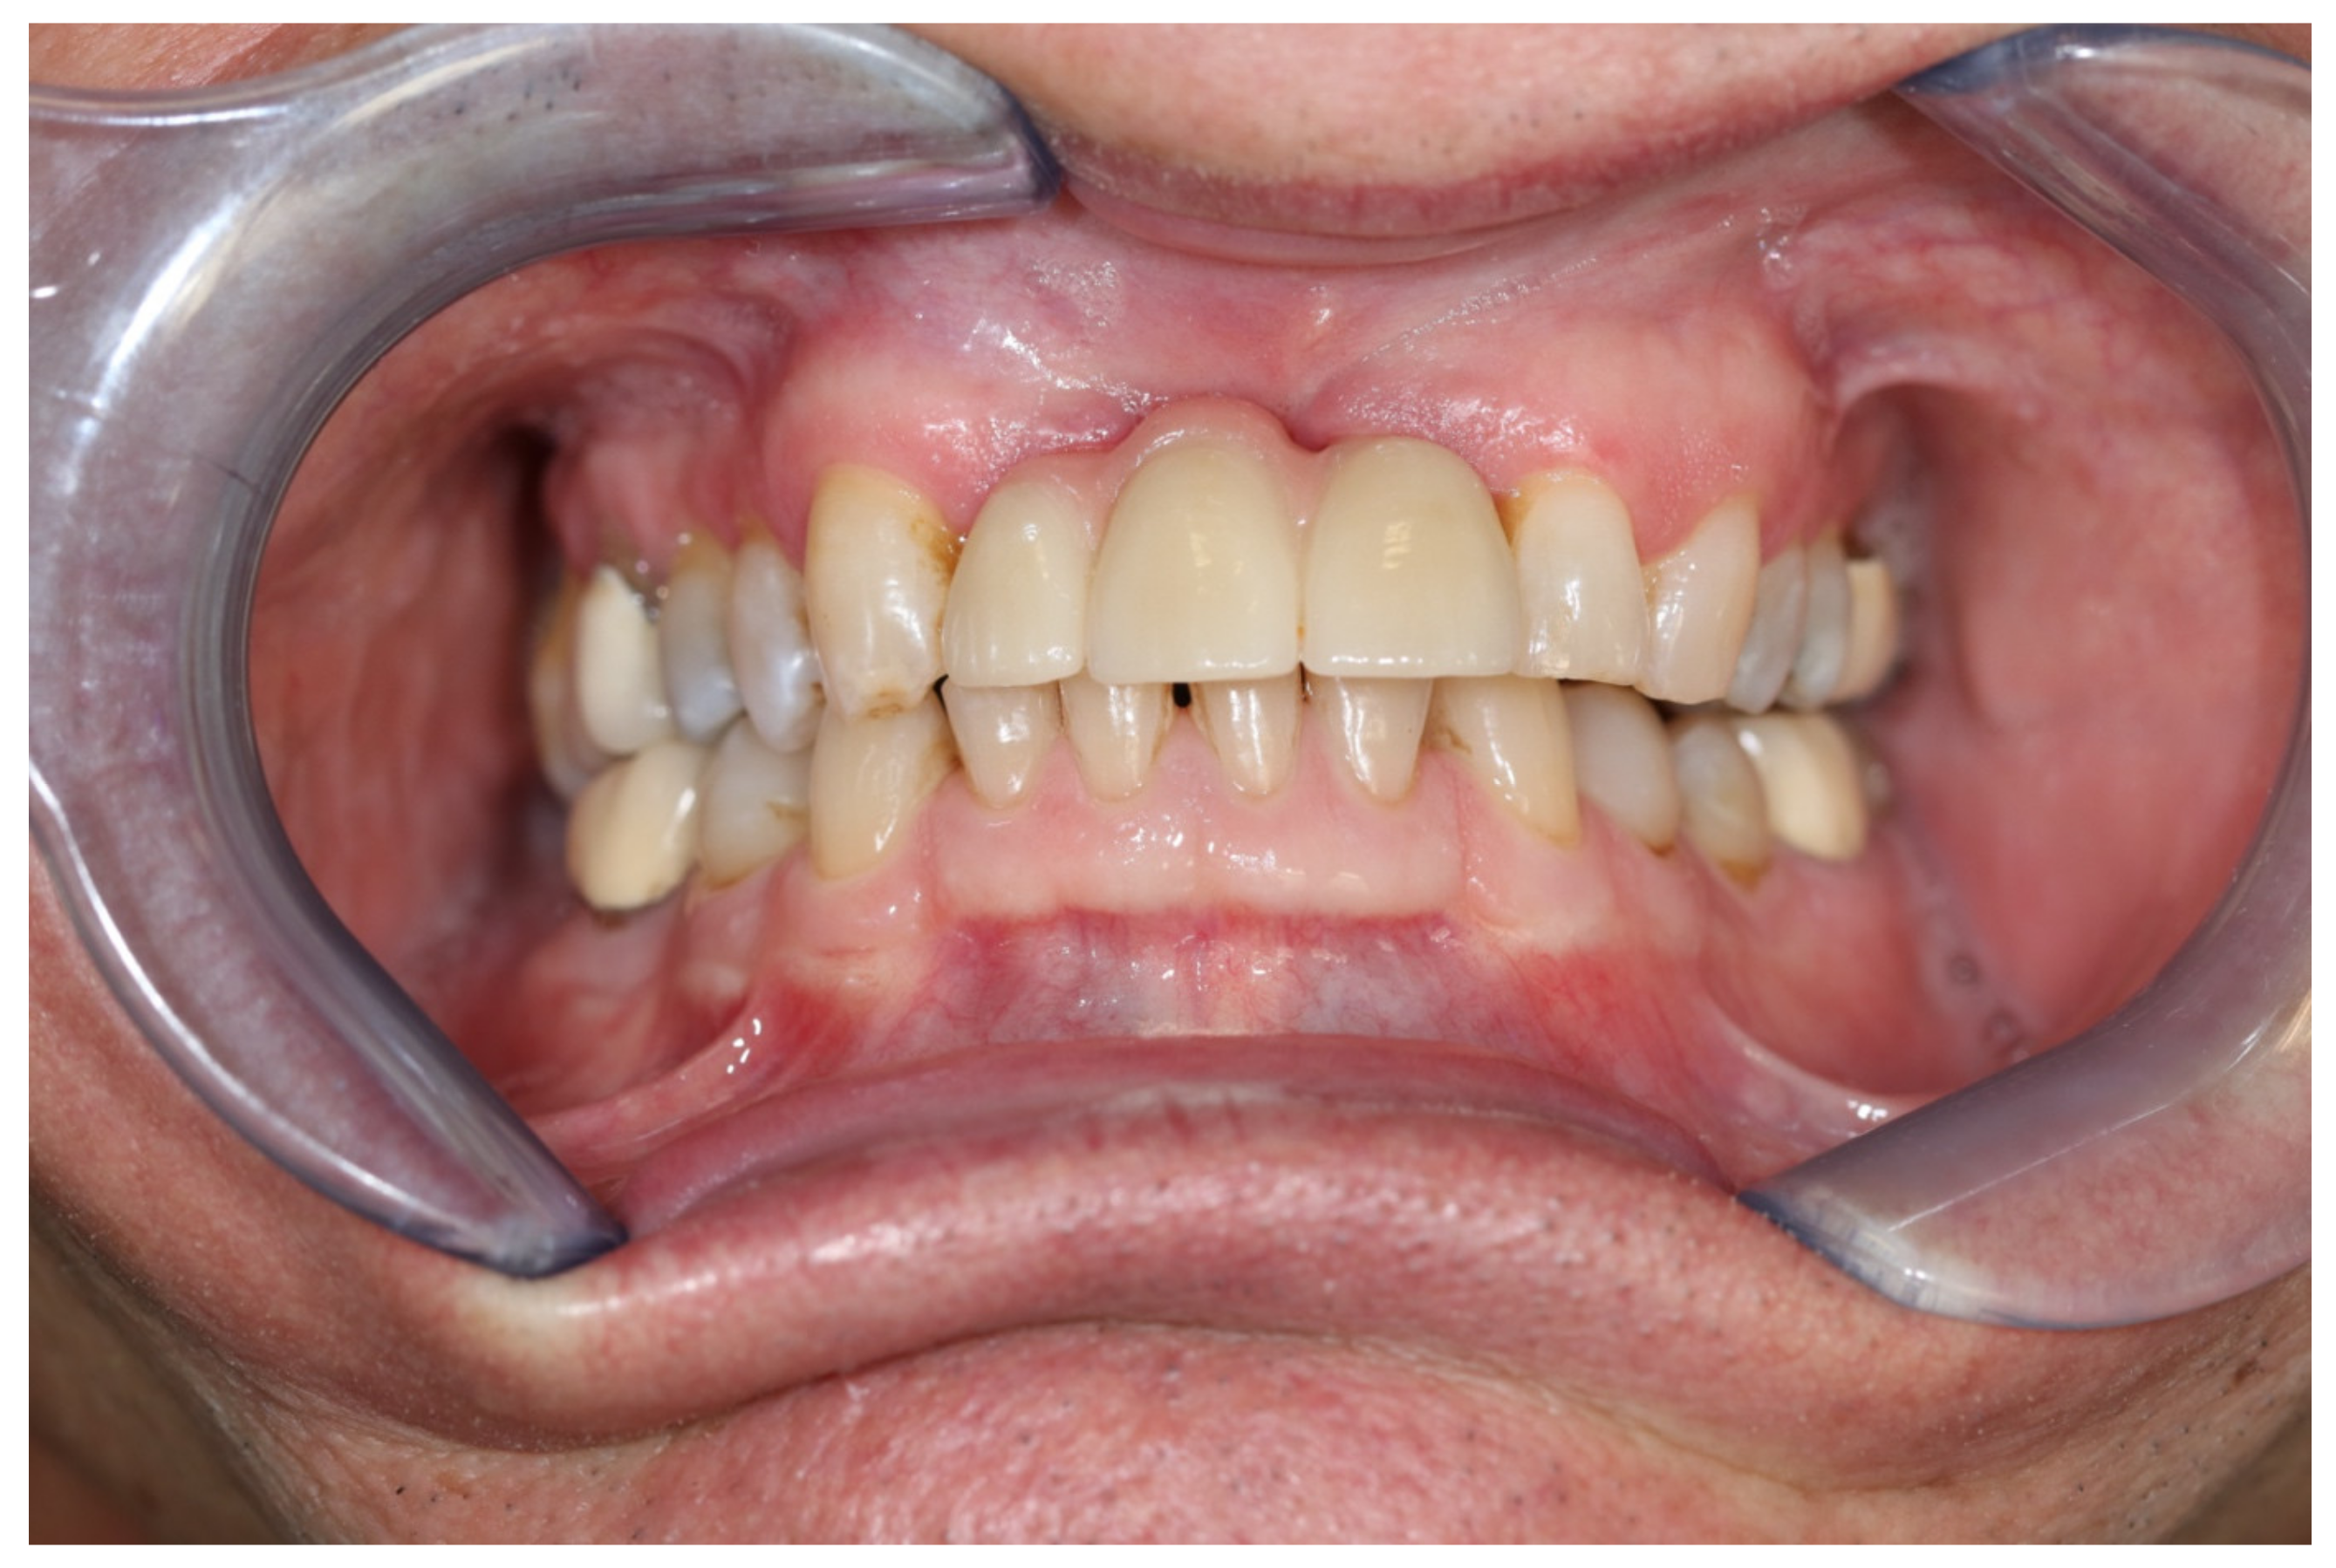

2. Case Report